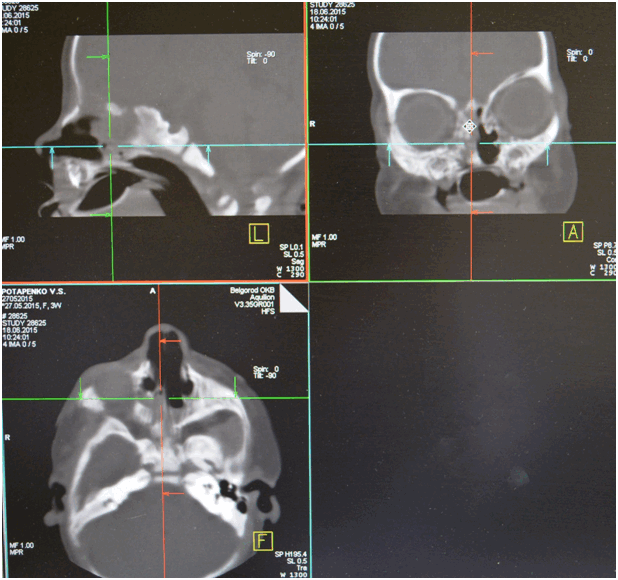

Для диагностики атрезии хоан используют разные методы: зондирование полости носа, рентгендиагностика с контрастным веществом. В настоящее время широкое применение получила компьютерная томография придаточных пазух носа. Двусторонние полные или частичные атрезии диагностируют у новорожденных и у детей раннего возраста. Односторонние частичные же атрезии хоан могут быть диагностированы и в более позднем возрасте, связано это с тем, что при таких атрезиях носовое дыхание лишь затруднено, а с одной стороны и вовсе не нарушено.

Из анамнеза известно, что указанные жалобы беспокоят с рождения. Ребенок родился в срок 40-41 неделя (27.05.2015), на фоне нарастания дыхательной недостаточности, через два часа после родов проведена интубация трахеи. Экстубация трахеи - 29.05.2015. С 01.06.2015 по 20.06.2015 с диагнозом нижнедолевая сегментарная правосторонняя пневмония, пиодермия, ринит, конъюнктивит девочка была на стационарном лечении в ОГБУЗ "Детской областной клинической больницы" г. Белгород. Проведено СКТ: картина двусторонней атрезии хоан. Рекомендовано консультация в НКЦО г. Москва. Ребёнок консультирован проф. Юнусову А.С. 22.06.2015 г. и направлен на хирургическое лечение в Отдел детской ЛОР патологии ФГБУ НКЦО ФМБА России.

Необходимо провести компьютерную томографию, так как она даст информацию о сопутствующих изменениях полости носа. Это позволит провести операцию по восстановлению просвета хоаны с учетом всех анатомических особенностей.